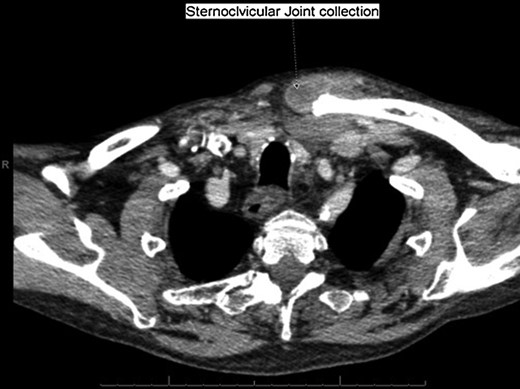

With a working differential of parapharyngeal space infection and possible malignancy, the patient was referred for a computed tomography (CT) scan of the neck and thorax with contrast. The patient was also started empirically on intravenous co-amoxiclav as treatment for neck space collection. CT imaging, performed 24 h after admission, revealed no evidence of malignancy or indeed any paraphayrngeal space collection. Few small lymph nodes were noted on the left side of the neck, but were deemed to be reactive in nature, and left vocal cord palsy was evident (Fig. 1). The key finding was that of a left sternoclavicular joint collection and closely associated superficial anterior chest wall, soft tissue swelling and oedema (Fig. 2). This inflammatory process was also noted deep to the manubrium and sternum and extending somewhat into the mediastinum with evident enlarged mediastinal lymph nodes (Fig. 3). The CT findings were in keeping with SSA with associated superficial and deep tissue inflammation and oedema. With no other cause found, the vocal cord palsy was attributed to the inflammation within the mediastinum, which in turn was caused by superficial burn from hot water bottle use.

Computed tomography. A 67-year-old male with SSA. Findings: left vocal cord palsy indicated by the para-median position of the left vocal cord in comparison with the right. Technique: contrast-enhanced axial CT of the neck and thorax.